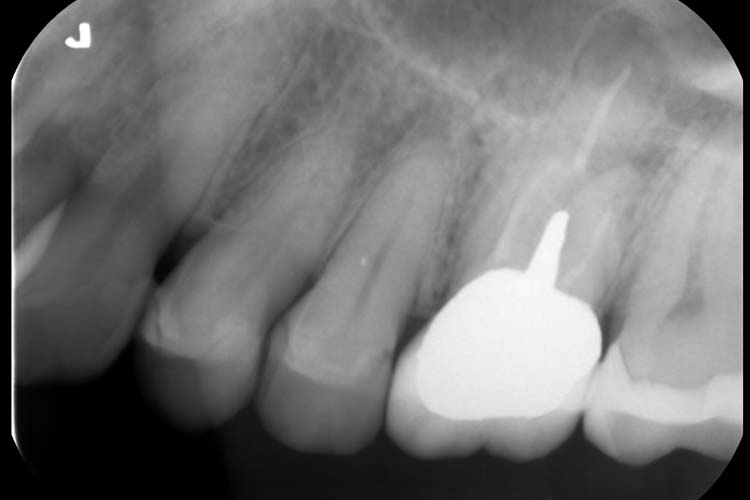

症例1

BEFORE

PROGRESS

AFTER

| 主訴 | 左上奥歯に違和感がある。 |

|---|---|

| 治療期間 | 5~6回 |

| 治療費 | 保険診療 |

| 治療内容 | 左上6番近心根に破折ファイルがあり、マイクロスコープ下で除去し、再根管治療を行った。 |

| 治療のリスク | 根管治療後、一時的に歯の根に痛みや違和感が生じることがあります。 |